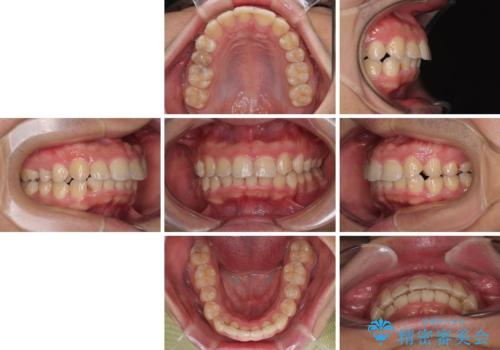

左右に顎がずれた咬み合わせ ワイヤー矯正で咬み合わせを改善

- デコボコと奥歯の咬み合わせのズレを気にして来院された患者様です。

骨格的に、下顎が右側にずれており、左側の咬み合わせに鋏状咬合などのアンバランスが生じている状態でした。

また、上顎前歯に欠損が1本あり、上下ともに前歯部に叢生が認められ、下顎前歯の大半が隠れてしまうほどの過蓋咬合も認められました。

咬合平面を平坦にしながら前歯の咬み合わせを挙上し、デコボコと鋏状咬合も改善していくこととしました。

骨格的な左右差が大きかったため、上下の正中のズレや、左右奥歯の咬み合わせなどは妥協的な仕上がりとなりました。

骨格的なズレに対応するにはワイヤー矯正が至適であり、マウスピース矯正は選択しないようにお話をしました。